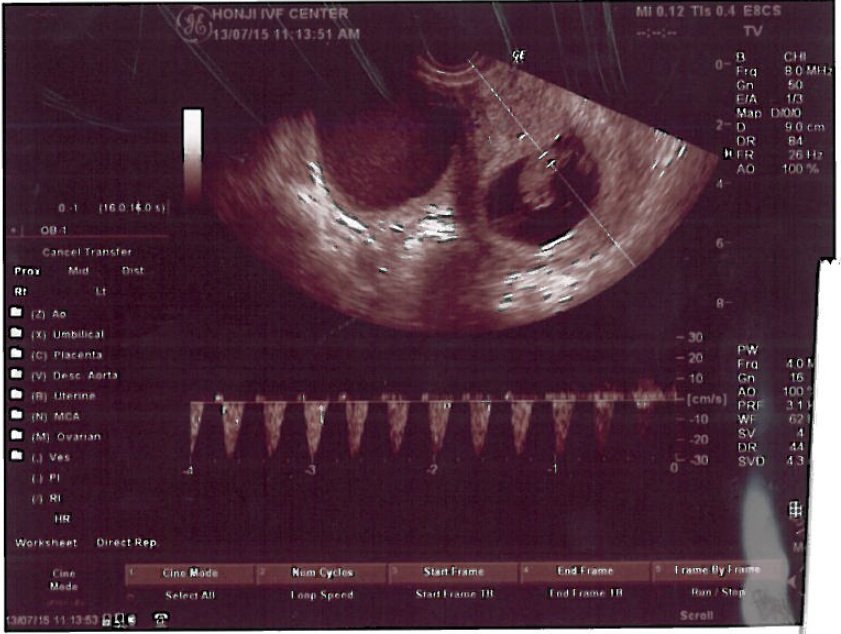

我们的过程算是有些特殊,因为是太太有些高龄(40岁)而且先生又有取精的问题(absence of ductus deferus 先天无输精管症),因此听说是一种较为困难毕业的例子。后来在张医师的疗程中,先是内人的少排卵针刺激及无麻醉取卵,再来是张医师亲自执行先生的无麻醉无开刀的副睪取精,然后马上在实验室精卵结合成受精卵并再约五天发育到囊胚,后才殖入终于顺利怀孕。并且无论是取卵还是取精,虽然副睪取精手术过程中还是有些疼痛与刺痛却尚在可忍受得住的范围,因为先前传统别家(北部医学中心)的经验是要全身麻醉手术且要数周的复原期,而张医师的治疗方式却是令人惊讶地手术后休息30分钟后马上可以走路回家,大约再需三天的稍稍疗养(除不能剧烈运动)后就仿佛如常人无手术般地复原了!

这次在张医师的精湛的手术、实验室团队的优良品管、怀孕初期的少量但精准的药物与数据控制,这次我们终于怀孕了,听到心跳的那一刹那,使我们体会到非常深刻的生命意义!